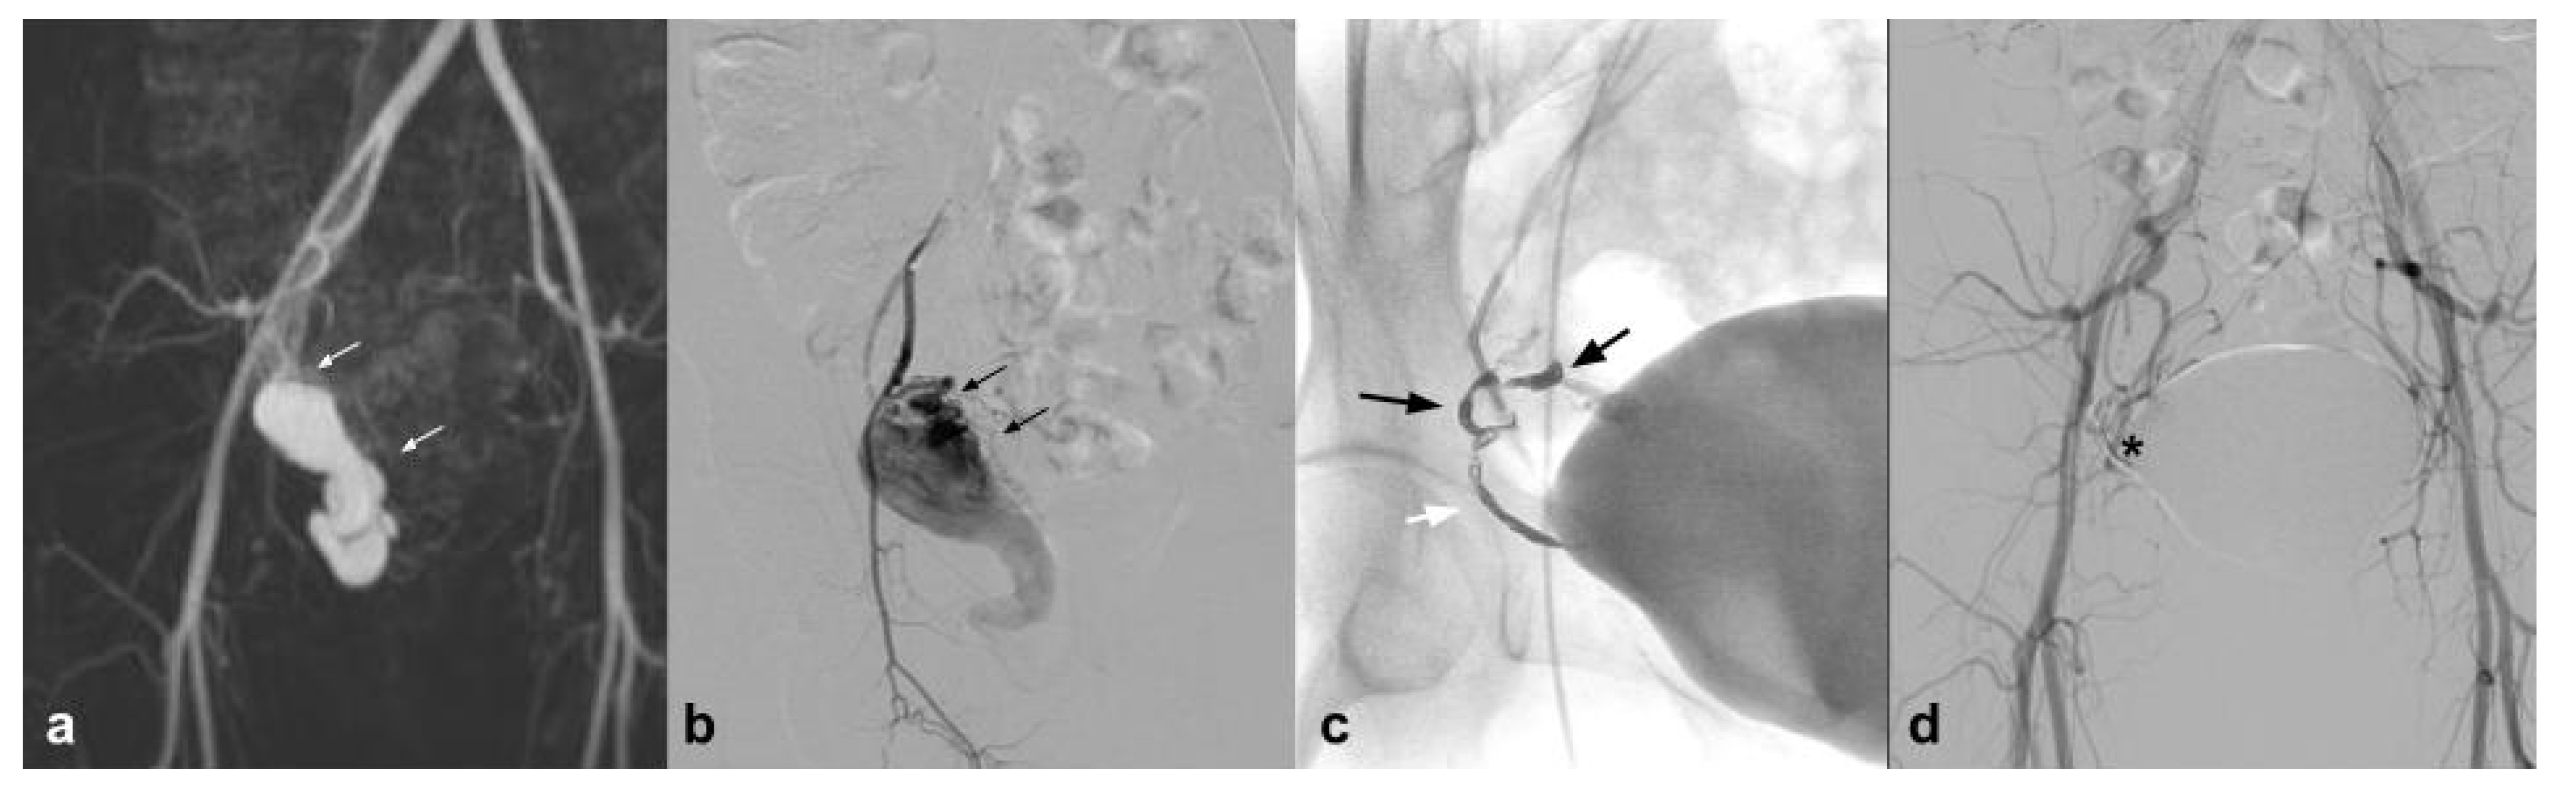

In addition to the peripheral district, which is perhaps the best represented in the literature, we can certainly talk about the uterine district, which is very well represented in literature; however, if we exclude emergency procedures and vascular malformations, the results refer to a few isolated experiences. In particular, the NALEAs are mentioned in a few papers with a single case series. AVM is a quite rare but potentially cause hemorrhages that can be life-threatening (Figure 1) [36].

Figure 1.

(a). Coronal CEMRA MIP demonstrates the presence of voluminous AVM originating from the right uterine artery with aneurysmal venous outflow (white arrows); (b) DSA performed with a vertebral shape catheter in the ipsilateral hypogastric artery confirms the presence of the AVM highlighting the “nidus” (black arrows); (c) single-shot post-treatment fluoroscopy shows the inferior uterine artery treated (white arrow) with coils (not directly tributary of the AVM) and the presence of a cast of Squid 12 at the level of the middle and inferior uterine artery which were the arterial feeding vessels of the AVM (black arrows); (d) post-procedure DSA demonstrates the complete exclusion of the treated AVM (asterisk).

Uterine AVMs are most commonly observed after pregnancy that occurs in women with a past history of induced abortion, curettage, uterine surgery, cesarean section, and diethylstilbestrol exposure. However, there is no consensus as to the type of embolization technique and the type of embolic agent. In this regard, several embolic agents have been used including particles, absorbable gelatin sponge, glue, and metallic coil [37]. The first work is that of Barral with a population of 12 patients, using Onyx as an embolizing agent, with excellent results. In this study, it is highlighted how EVOHs are ideal in the tortuosity of the uterine vessels in case of AVM. In addition, two pregnancies are reported after embolization with Onyx [36]. Another work in which some cases of uterine AVM are cited is the review by Venturini et al., in which Squid is used as an embolic agent, with excellent results [13].